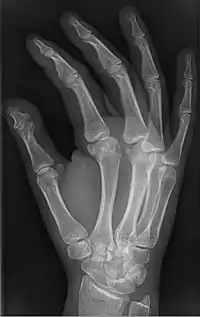

Brachyphalangy is a condition in which one or more of the phalanges of the fingers and toes are smaller than normal.[1]

This condition is one of the most common non-syndromic causes of brachydactyly and clinodactyly.